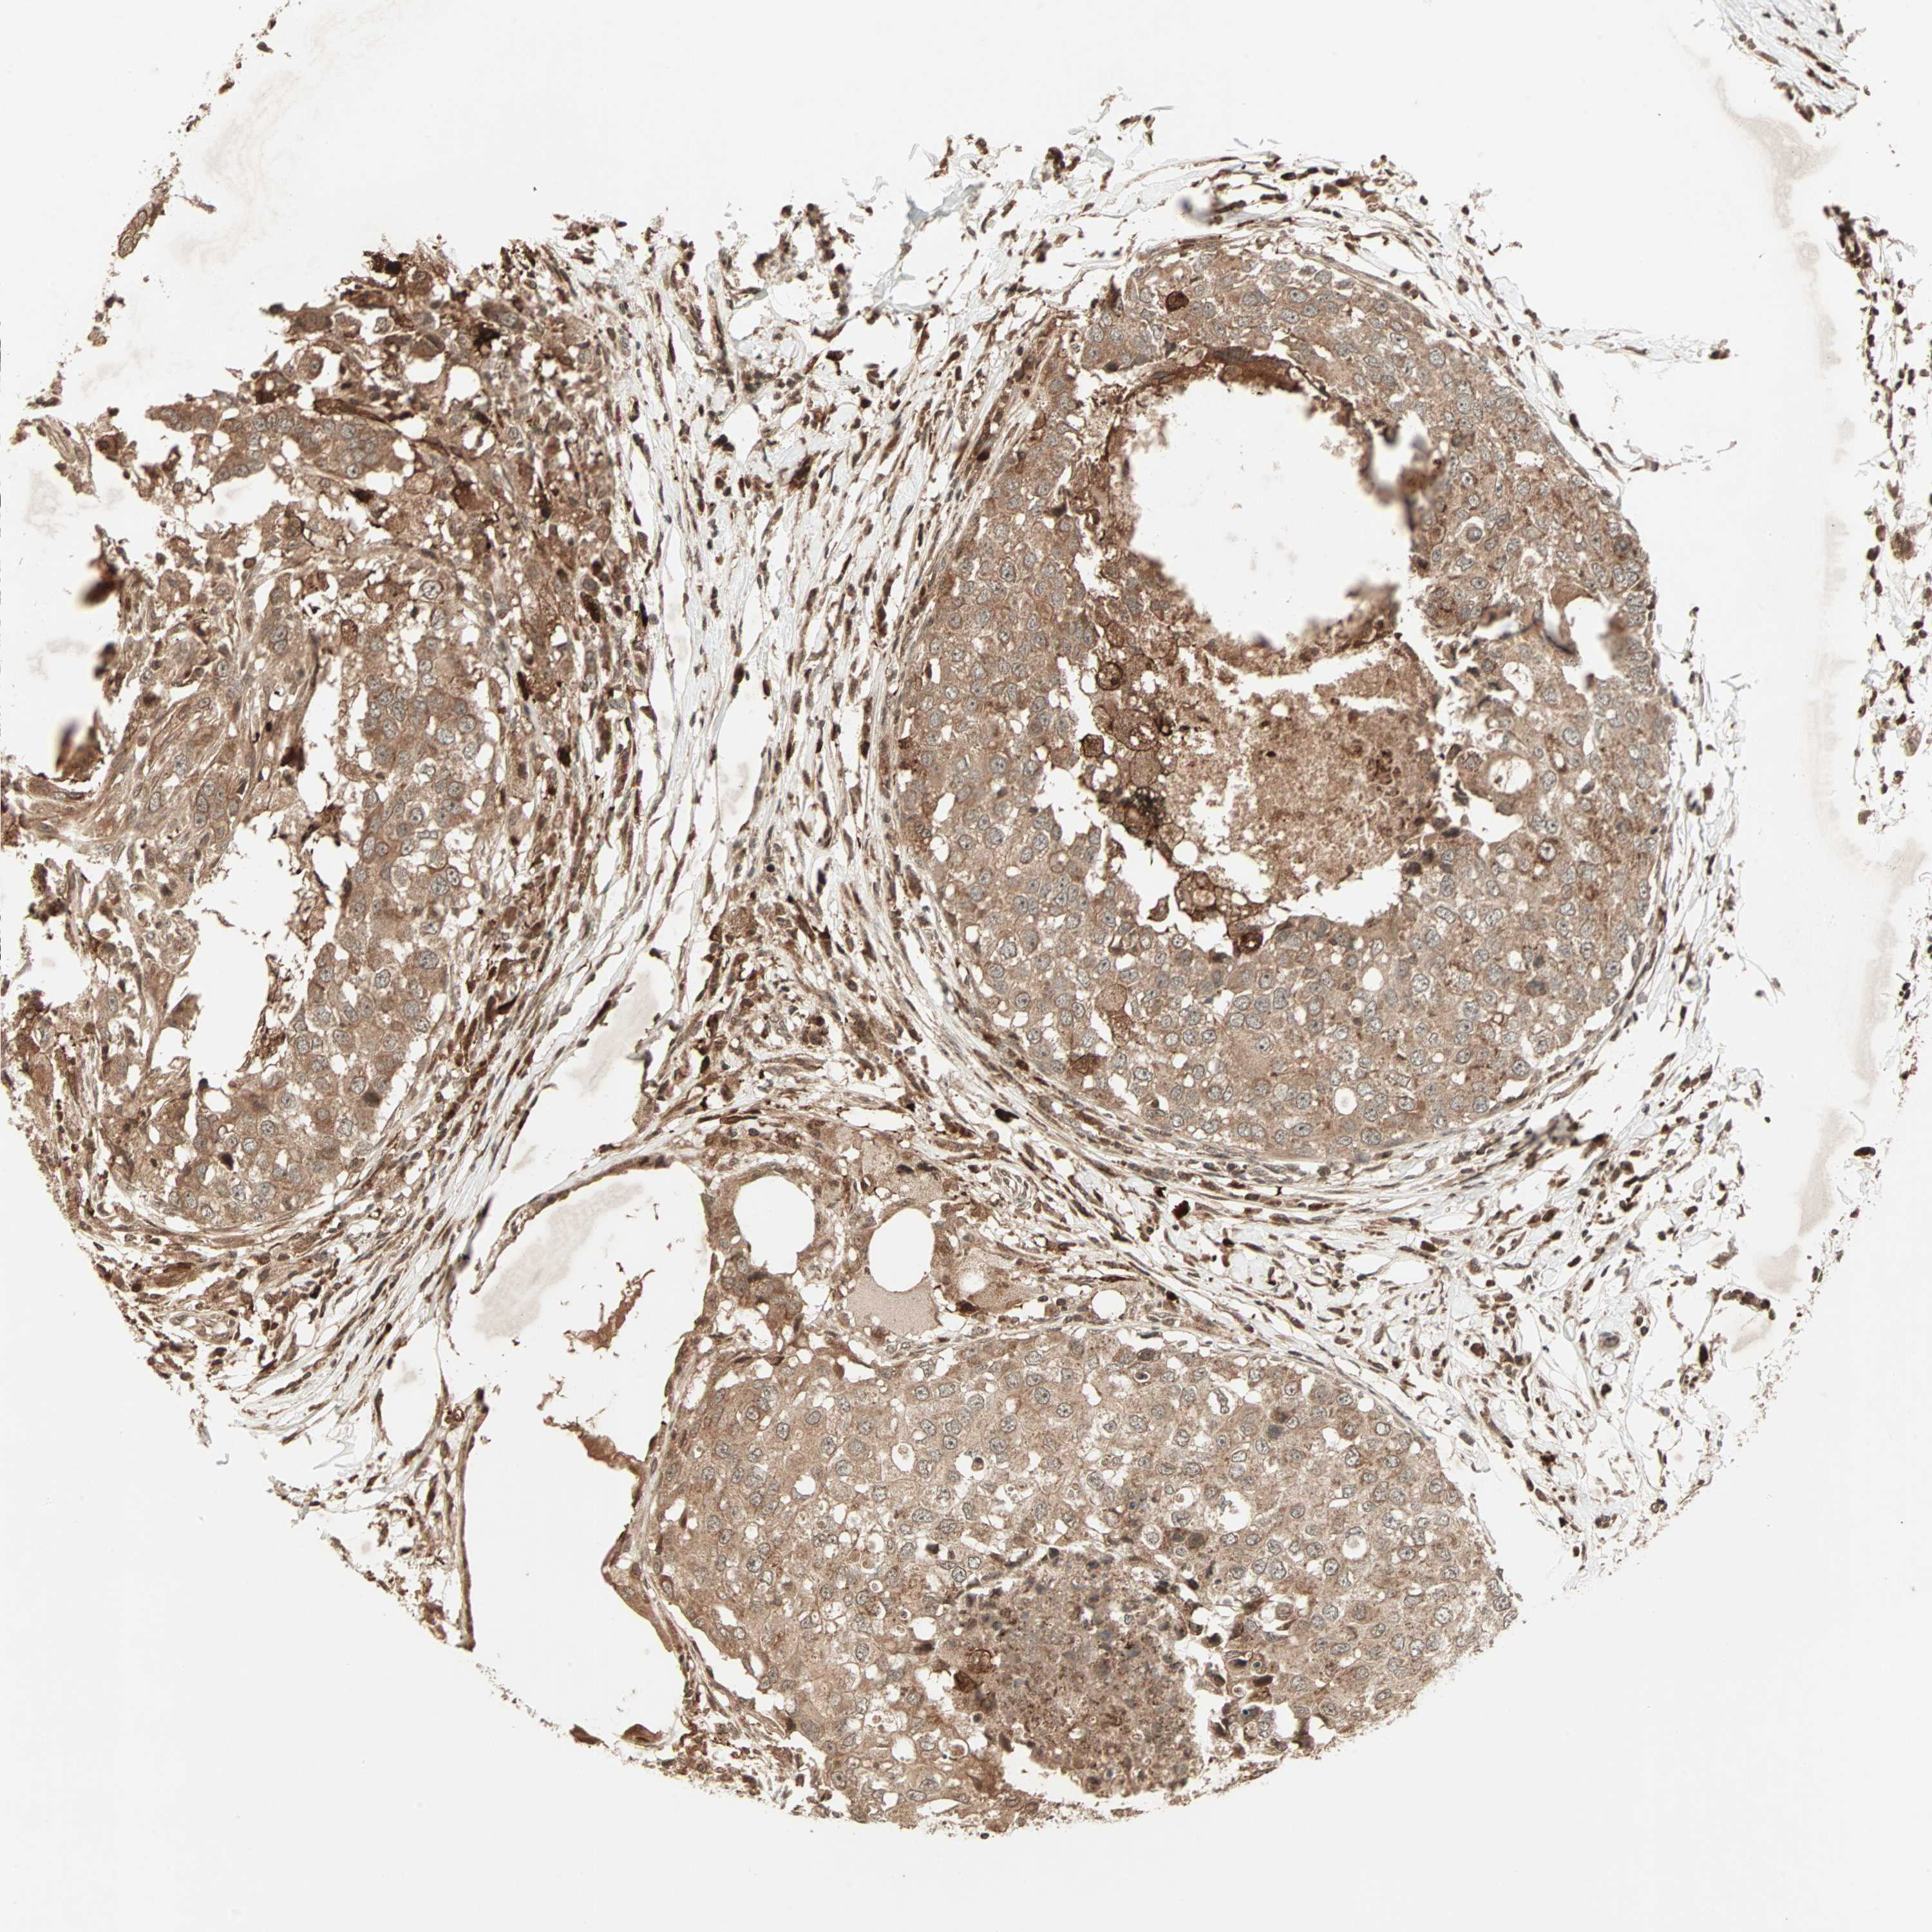

BRCA TCGA BRCA VALIDATION PROTEIN EXPRESSION

ANTIBODIES

AND

VALIDATION